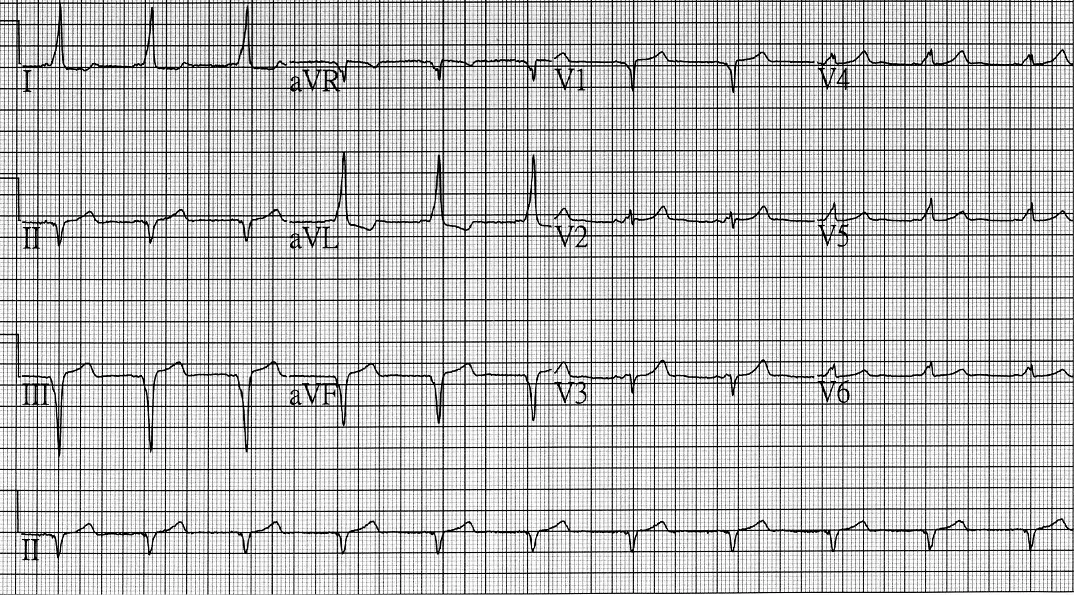

一位 44 歲女性因心悸至門診檢查,心電圖顯示如下圖,其附屬路徑或旁道( accessory pathway )最可能位在何處?

本題 12 導程心電圖顯示以下特徵:

WPW 特徵確認:

- PR 間期縮短(< 120 ms):房室結以外的附屬路徑允許衝動提早抵達心室

- Delta 波(QRS 起始部分的斜面/模糊上升段):心室預激的直接證據

- QRS 寬化:融合波(fusion beat),正常 His-Purkinje 傳導與旁道傳導同時存在

旁道定位分析:

- 下壁導程(II、III、aVF):可見 delta 波呈負向或等電位(negative/isoelectric),提示旁道位於後方(posterior)

- 下壁負向 delta 波為後方旁道的重要定位依據

- III 和 aVF 的負向